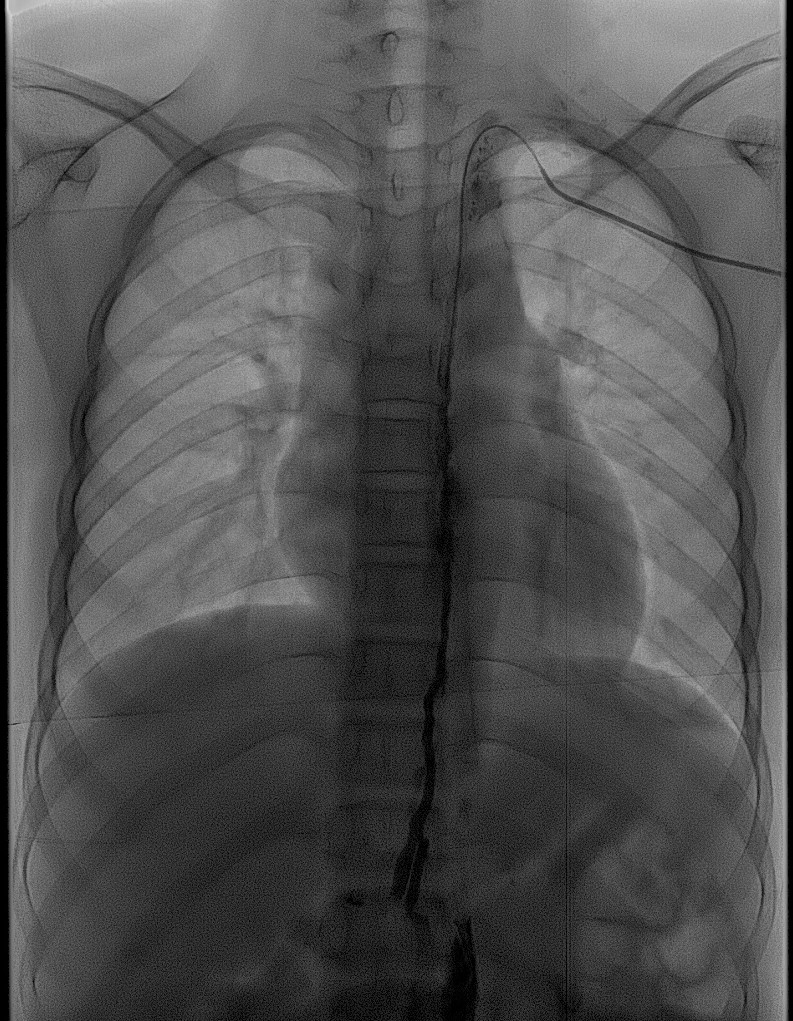

春节临近,四川大学华西第二医院放射科刘灵军博士带领介入医技护团队,成功为一例阴道乳糜瘘的13岁女性患儿以介入方式进行了“淋巴造影+硬化治疗手术”。在超声科万晋州老师的超声精准定位引导下,刘灵军博士用穿刺针进入直径不到1cm的淋巴结,然后在DSA监视下顺利实施淋巴结内造影及硬化治疗,同时经贵要静脉行胸导管逆行造影和疏通术。经过近7小时的奋战,手术非常成功。

该患儿患阴道乳糜瘘10多年,能明显感觉到会阴部不自主漏液,每日漏夜可完全浸湿6-8片尿不湿,生活质量差,严重影响患儿的身心健康。患儿父母带着患儿四处求医,辗转多家医院治疗无果后找到我院放射科介入亚专业组长刘灵军博士。刘灵军博士在充分了解患儿病情后,积极主动与临床多学科讨论,结合影像学检查诊断为“腹盆腔淋巴管发育畸形,与生殖系统有交通的异常发育的淋巴管破裂导致阴道乳糜瘘”,有介入手术指征。此类病例文献报道罕见,缺少成熟完整的手术方案。介入诊疗团队通过研究决定,在超声引导下穿刺腹股沟淋巴结行“淋巴造影和硬化治疗”,同时经贵要静脉行“胸导管逆行造影和疏通术”。医技护团队通力合作,连续奋战7个小时,以辛勤的汗水与精湛的技术相结合,顺利完成预定诊疗进程,术中患儿就自觉阴道漏液感消失,术后恢复良好。